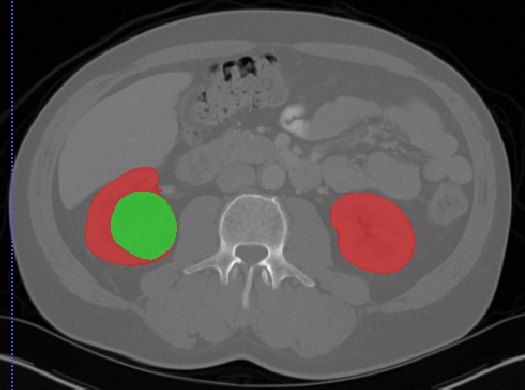

# 肾脏

## Kits19

| [Kits19](https://kits19.grand-challenge.org/) | 肾脏/肾肿瘤 | 分割 | | | | | |